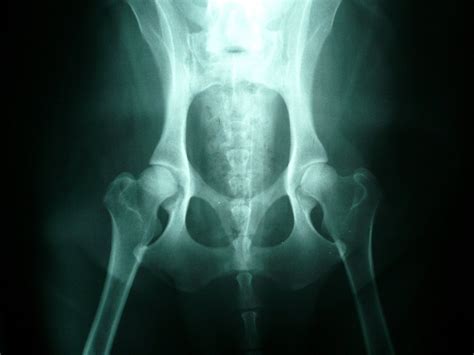

Pre čistokrvný chov sa môžu používať len čistokrvné jedince zapísané v plemenných knihách členských krajín FCI, zaradené do chovu po splnení podmienok určených príslušným chovateľským klubom. Podmienkou pre zaradenie do chovu u SČ je absolvovanie bonitácie. Pre účasť na bonitácii je predpísaný minimálny vek 18 mesiacov v deň konania bonitácie, absolvovanie dvoch výstav, RTG na dyspláziu bedrových kĺbov s výsledkom maximálne do druhého stupňa. Jedince s vyšším stupňom sa môžu zaradiť do chovu podľa zváženia bonitačnej komisie pri mimoriadnych kvalitách exteriéru.

| RTG dysplázia bedrových kĺbov | Maximálne 2. stupeň |